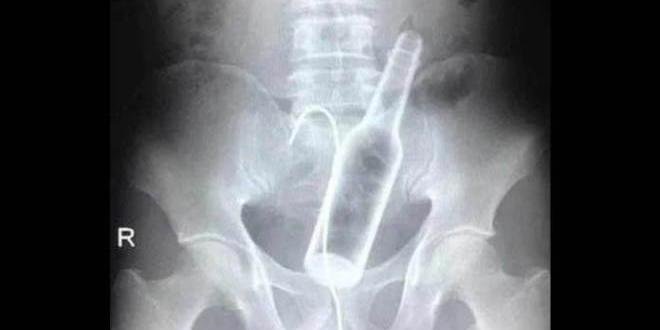

Imagem: Divulgação

Um homem precisou passar por um procedimento cirúrgico para remover uma garrafa do reto, após introduzi-la no ânus e não conseguir tirar. O caso ocorreu em um município chamado Brasiléia, no Acre.

O homem com cerca de 25 anos estava alcoolizado, quando decidiu ‘brincar’ com o objeto. Só não contava que a garrafa ficaria presa. Sem ter como remover sozinho, ele pediu socorro ao Samu (Serviço de Atendimento Móvel de Urgência), e foi conduzido ao hospital regional.

Como foi constatado perigo à saúde e vida do homem, ele precisou ser removido para a capital, Rio Branco. A cirurgia para remoção da garrafa foi bem sucedida e o paciente recebeu alta hospitalar. Questionado sobre o procedimento adotado para a retirada, o médico responsável preferiu não dar detalhes.